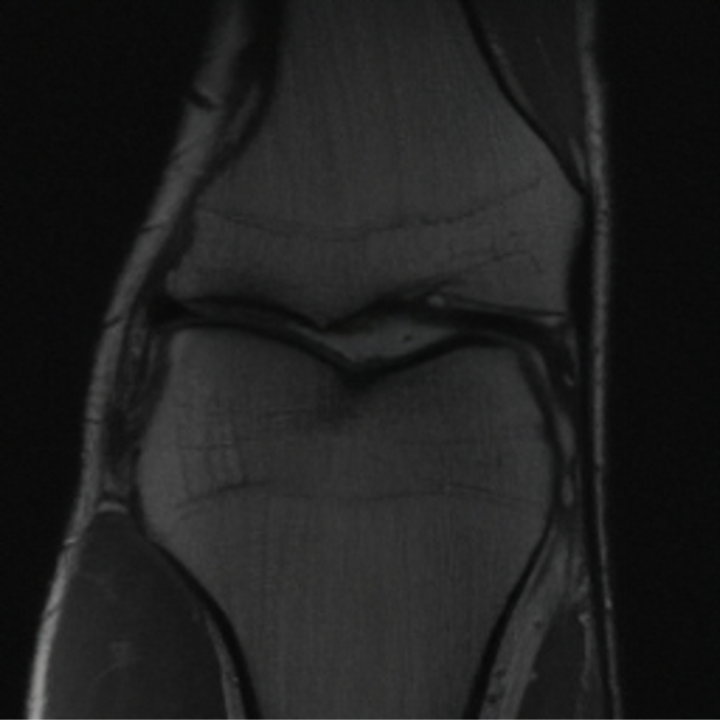

5.3 Out-of-Domain Generalisation

One way to test the generalization capability of the trained X-Diffusion is to test it on a completely different domain from an MRI dataset not seen during training. We report the single-slice results on NYU fastMRI [37, 82], a knee MRI dataset, using the X-Diffusion trained on the BRATS brain MRIs. The results are shown in Figure 9 and Table 2. It shows how successfully X-Diffusion is able to generate knee MRIs from a single image, despite not seeing knees at all in training. To qualitatively assess how realistic our generated 3D volumes were (produced from a single slice), we gave 20 generated examples alongside their real MRI counterparts to an expert orthopaedic surgeon. He was then asked to identify the real example from a given pair. The surgeon identified with certainty only 10 real knee MRIs out of 17, while could not decide on the remaining 3 of the 20 MRI pairs. This further validates the generated out-of-domain MRIs.